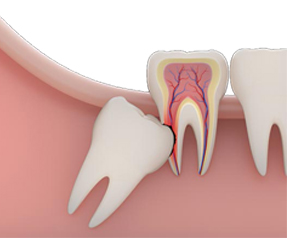

GÖMÜK DİŞLER